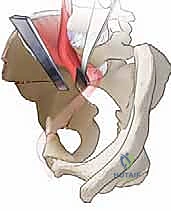

الخطوة الثانية: الشق الجراحي والوصول الآمن

يتم عمل شق جراحي تجميلي في الجزء الأمامي من الحوض. تُفصل العضلات بلطف شديد (دون قطعها قدر الإمكان) للوصول إلى عظام الحوض المحيطة بمفصل الورك، مع الحفاظ التام على الأعصاب والأوعية الدموية الرئيسية.